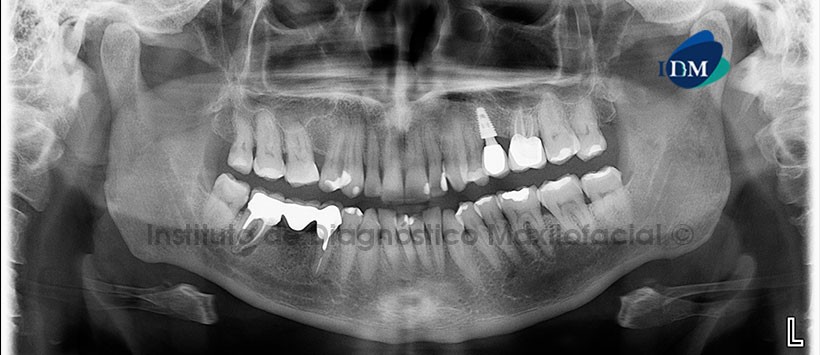

En la radiografía panorámica (Figura 1) se observa múltiples restauraciones e implante con prótesis sobre implante en pieza 25. Obturación de conductos en piezas 26, 45 y 47, observándose un proceso osteolítico periapical e inter-radicular en pieza 47.